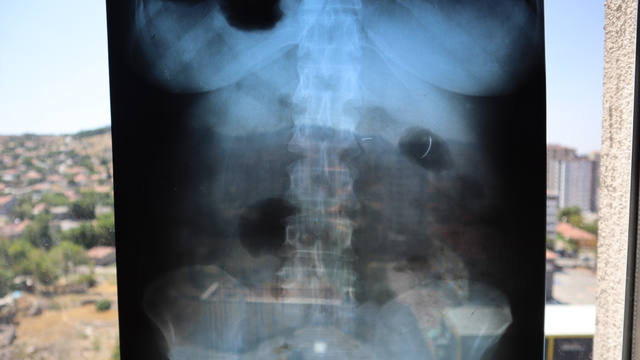

Kentte yaşayan 2 çocuk annesi Ayhan Tanyıldız, 2003 yılında karaciğerindeki kist nedeniyle ameliyat oldu. Ameliyat olduktan 6 yıl sonra böbrek rahatsızlığı nedeniyle hastaneye giden Tanyıldız’ın çekilen röntgeninde iğne görüldü. Tanyıldız’ın kist ameliyatı sırasında karnında ameliyat iğnesi unutulduğu ortaya çıktı. Kendisini özel hastanede ameliyat eden Genel Cerrahi Doktoru İ.D.’ye dava açan Tanyıldız, ağrılarının nedeninin karnında unutulan ameliyat iğnesi olduğunu öğrendi. 19 yıl sonra mahkemesi de sonuçlanan Tanyıldız, bir miktar tazminat almaya hak kazandı. 22 yıldır ameliyat iğnesiyle yaşayan Tanyıldız, “2003 yılında ameliyatım yapıldı. Karaciğerimdeki kistten dolayı ameliyat oldum. Karaciğerimde kist oluşmuş. Kisti alırken ameliyat iğnesini unutmuşlar. 6 yıl sonra fark ettim. İlk öğrendiğimde başka doktora gittim, böbreklerimden rahatsızlanmıştım. Doktor film çekince ‘sen MR’a girme, ciğerinde iğne var’ dedi. O zaman fark ettim. Fiziksel olarak hala ağrısını, yıllardır çekiyorum” diye konuştu.

“İğne 22 yıldır çıkarılmadı. Riskli olduğu için çıkaramıyorlar. Kanamayı durduramayacakları için, iğne ciğerimde geziyor. Açınca iğneyi bulamayacakları için, kimse o riski almak istemiyor. İnşallah bir doktor çıkar. Beni bu sıkıntıdan, 22 yıllık çektiğim çilelerden kurtarırsa çok mutlu olurum, dua ederim.”